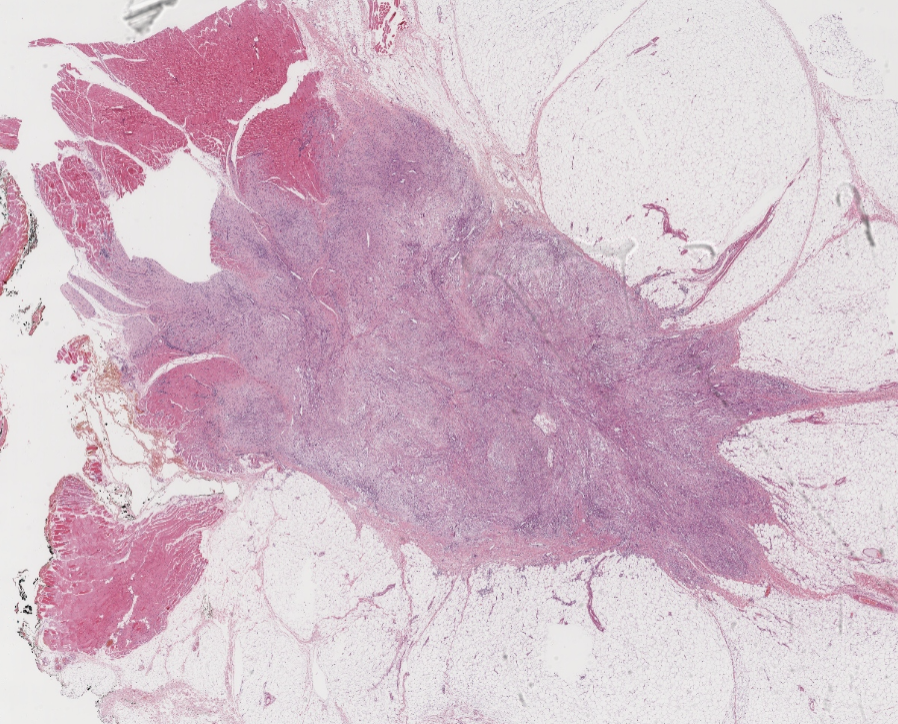

Ulcerated mass in the colon. ▶️Geographic necrosis ▶️Lots of mitoses & apoptotic bodies ▶️Sheet-like & trabecular growth ▶️Highly atypical nuclei w/ prominent nucleoli ▶️Eosinophilic cytoplasm Based on 🔬H&E morphology, what is your diagnosis? #PathTwitter #GIPath

Miruna Popescu, MD tweet mediaMiruna Popescu, MD tweet mediaMiruna Popescu, MD tweet mediaMiruna Popescu, MD tweet media